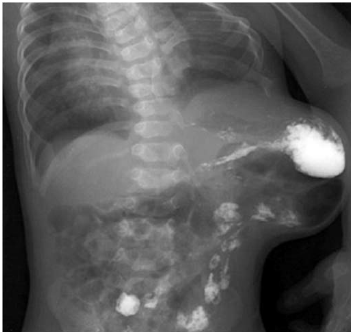

Disponível em: <www.radiology.con.mk>. Acesso em: 16 fev. 2023.

Um paciente, procurou atendimento em ambulatório de cirurgia geral com queixa de abaulamento na região lateral do abdome há dois anos. Em razão da falta de recursos naquela região, foram realizados raios X de tórax e abdome. Com base na imagem apresentada, a principal hipótese diagnóstica para o paciente é hérnia de